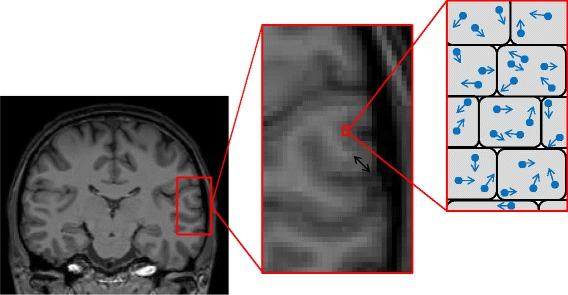

Alzheimer's disease (AD) is recognized to have a long presymptomatic period, during which there is progressive accumulation of molecular pathology, followed by inexorable neuronal damage. The ability to identify presymptomatic individuals with evidence of neurodegenerative change, to stage their disease, and to track progressive changes will be important for early diagnosis and for prevention trials. Despite recent advances, particularly in magnetic resonance imaging, our ability to identify early neurodegenerative changes reliably is limited. The development of diffusion-weighted magnetic resonance imaging, which is sensitive to microstructural changes not visible with conventional volumetric techniques, has led to a number of diffusion imaging studies in AD; these have largely focused on white matter changes. However, in AD cerebral grey matter is affected very early, with pathological studies suggesting that grey matter changes predate those in white matter. In this article we review the growing number of studies that assess grey matter diffusivity changes in AD. Although use of the technique is still at a relatively early stage, results so far have been promising. Initial studies identified changes in diffusion measures in the hippocampi of patients with mild cognitive impairment, which predated macroscopic volume loss, with positive predictive value for progression to AD dementia. More recent studies have identified abnormalities in multiple neocortical areas (particularly the posterior cingulate) at various stages of disease progression. Studies of patients who carry genetic mutations predisposing to autosomal dominant familial AD have shown cortical and subcortical grey matter diffusivity changes several years before the expected onset of the first clinical symptoms. The technique is not without potential methodological difficulties, especially relating to partial volume effects, although recent advances appear to be reducing such issues. Going forward, further utilization of grey matter diffusion measurements in AD may improve our understanding with regards to the timing and nature of the earliest presymptomatic neurodegenerative changes. This imaging technique may also be useful in comparing and contrasting subtle variations in different disease subgroups, and as a sensitive outcome measure for presymptomatic clinical trials in AD and other neurodegenerative diseases.

阿尔茨海默病(AD)被认为有很长的症状前期,在此期间分子病理学改变会逐渐累积,随后不可避免地出现神经元损伤。识别有神经退行性改变证据的症状前个体、对其疾病进行分期以及追踪病情进展变化的能力,对于早期诊断和预防试验至关重要。尽管最近取得了进展,尤其是在磁共振成像方面,但我们可靠识别早期神经退行性改变的能力仍然有限。扩散加权磁共振成像的发展,它对传统容积技术无法看到的微观结构变化敏感,已引发了多项针对AD的扩散成像研究;这些研究主要集中在白质变化上。然而,在AD中脑灰质很早就受到影响,病理研究表明灰质变化早于白质变化。在本文中,我们回顾了越来越多评估AD中灰质扩散率变化的研究。尽管该技术的应用仍处于相对早期阶段,但迄今为止的结果很有前景。最初的研究发现轻度认知障碍患者海马体的扩散测量值发生变化,这早于宏观体积损失,对进展为AD痴呆具有阳性预测价值。最近的研究在疾病进展的各个阶段都发现多个新皮质区域(特别是后扣带回)存在异常。对携带常染色体显性家族性AD易感基因突变患者的研究表明,在预期首次出现临床症状前数年,皮质和皮质下灰质扩散率就发生了变化。该技术并非没有潜在的方法学困难,尤其是与部分容积效应有关的问题,不过最近的进展似乎正在减少此类问题。展望未来,在AD中进一步利用灰质扩散测量可能会增进我们对最早症状前神经退行性改变的时间和性质的理解。这种成像技术也可能有助于比较和对比不同疾病亚组中的细微差异,并作为AD和其他神经退行性疾病症状前临床试验的敏感结局指标。